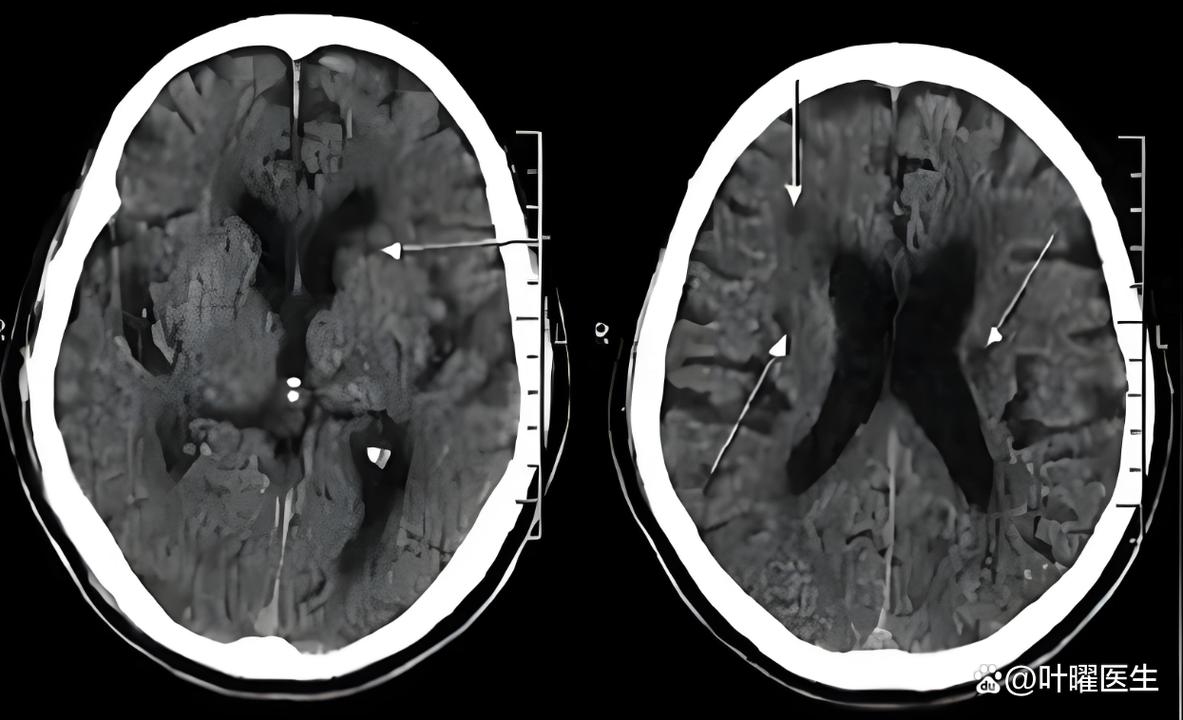

(图片来源网络,侵删)这指的是检查的部位和方法,即“头颅核磁共振成像”(MRI),这是一种非常先进的影像学检查,对脑部组织的分辨率很高,能发现CT检查看不出来的细微病变。

腔梗:

(图片来源网络,侵删)- 这是核心诊断。“腔隙性脑梗塞”的简称。

- 形成原因:我们的大脑里有非常细小的血管,叫做“穿通动脉”,这些血管为大脑深部的一些重要结构(如基底节、丘脑、脑干等)供血,当这些小血管因为各种原因(比如堵塞、变性)发生堵塞时,它所供应的那一小块脑组织就会因为缺血而坏死,形成一个微小的“洞”或“腔隙”,这个坏死区域就叫做“腔隙性脑梗塞”。